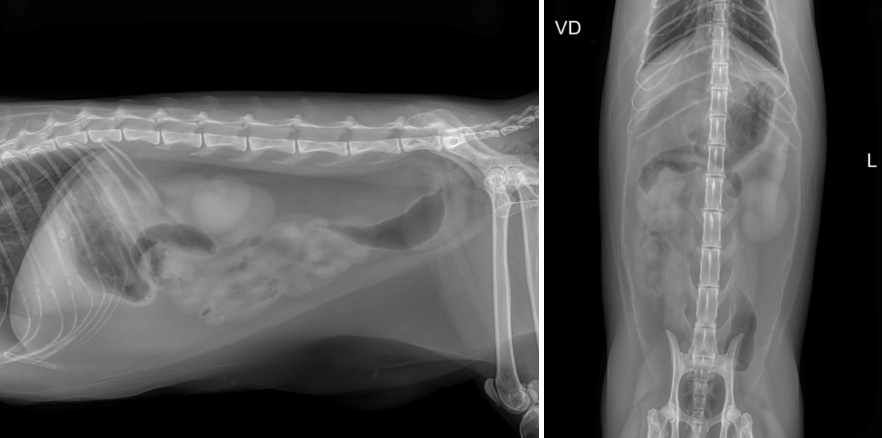

x-ray 검사상 특이소견은 확인되지 않았습니다.